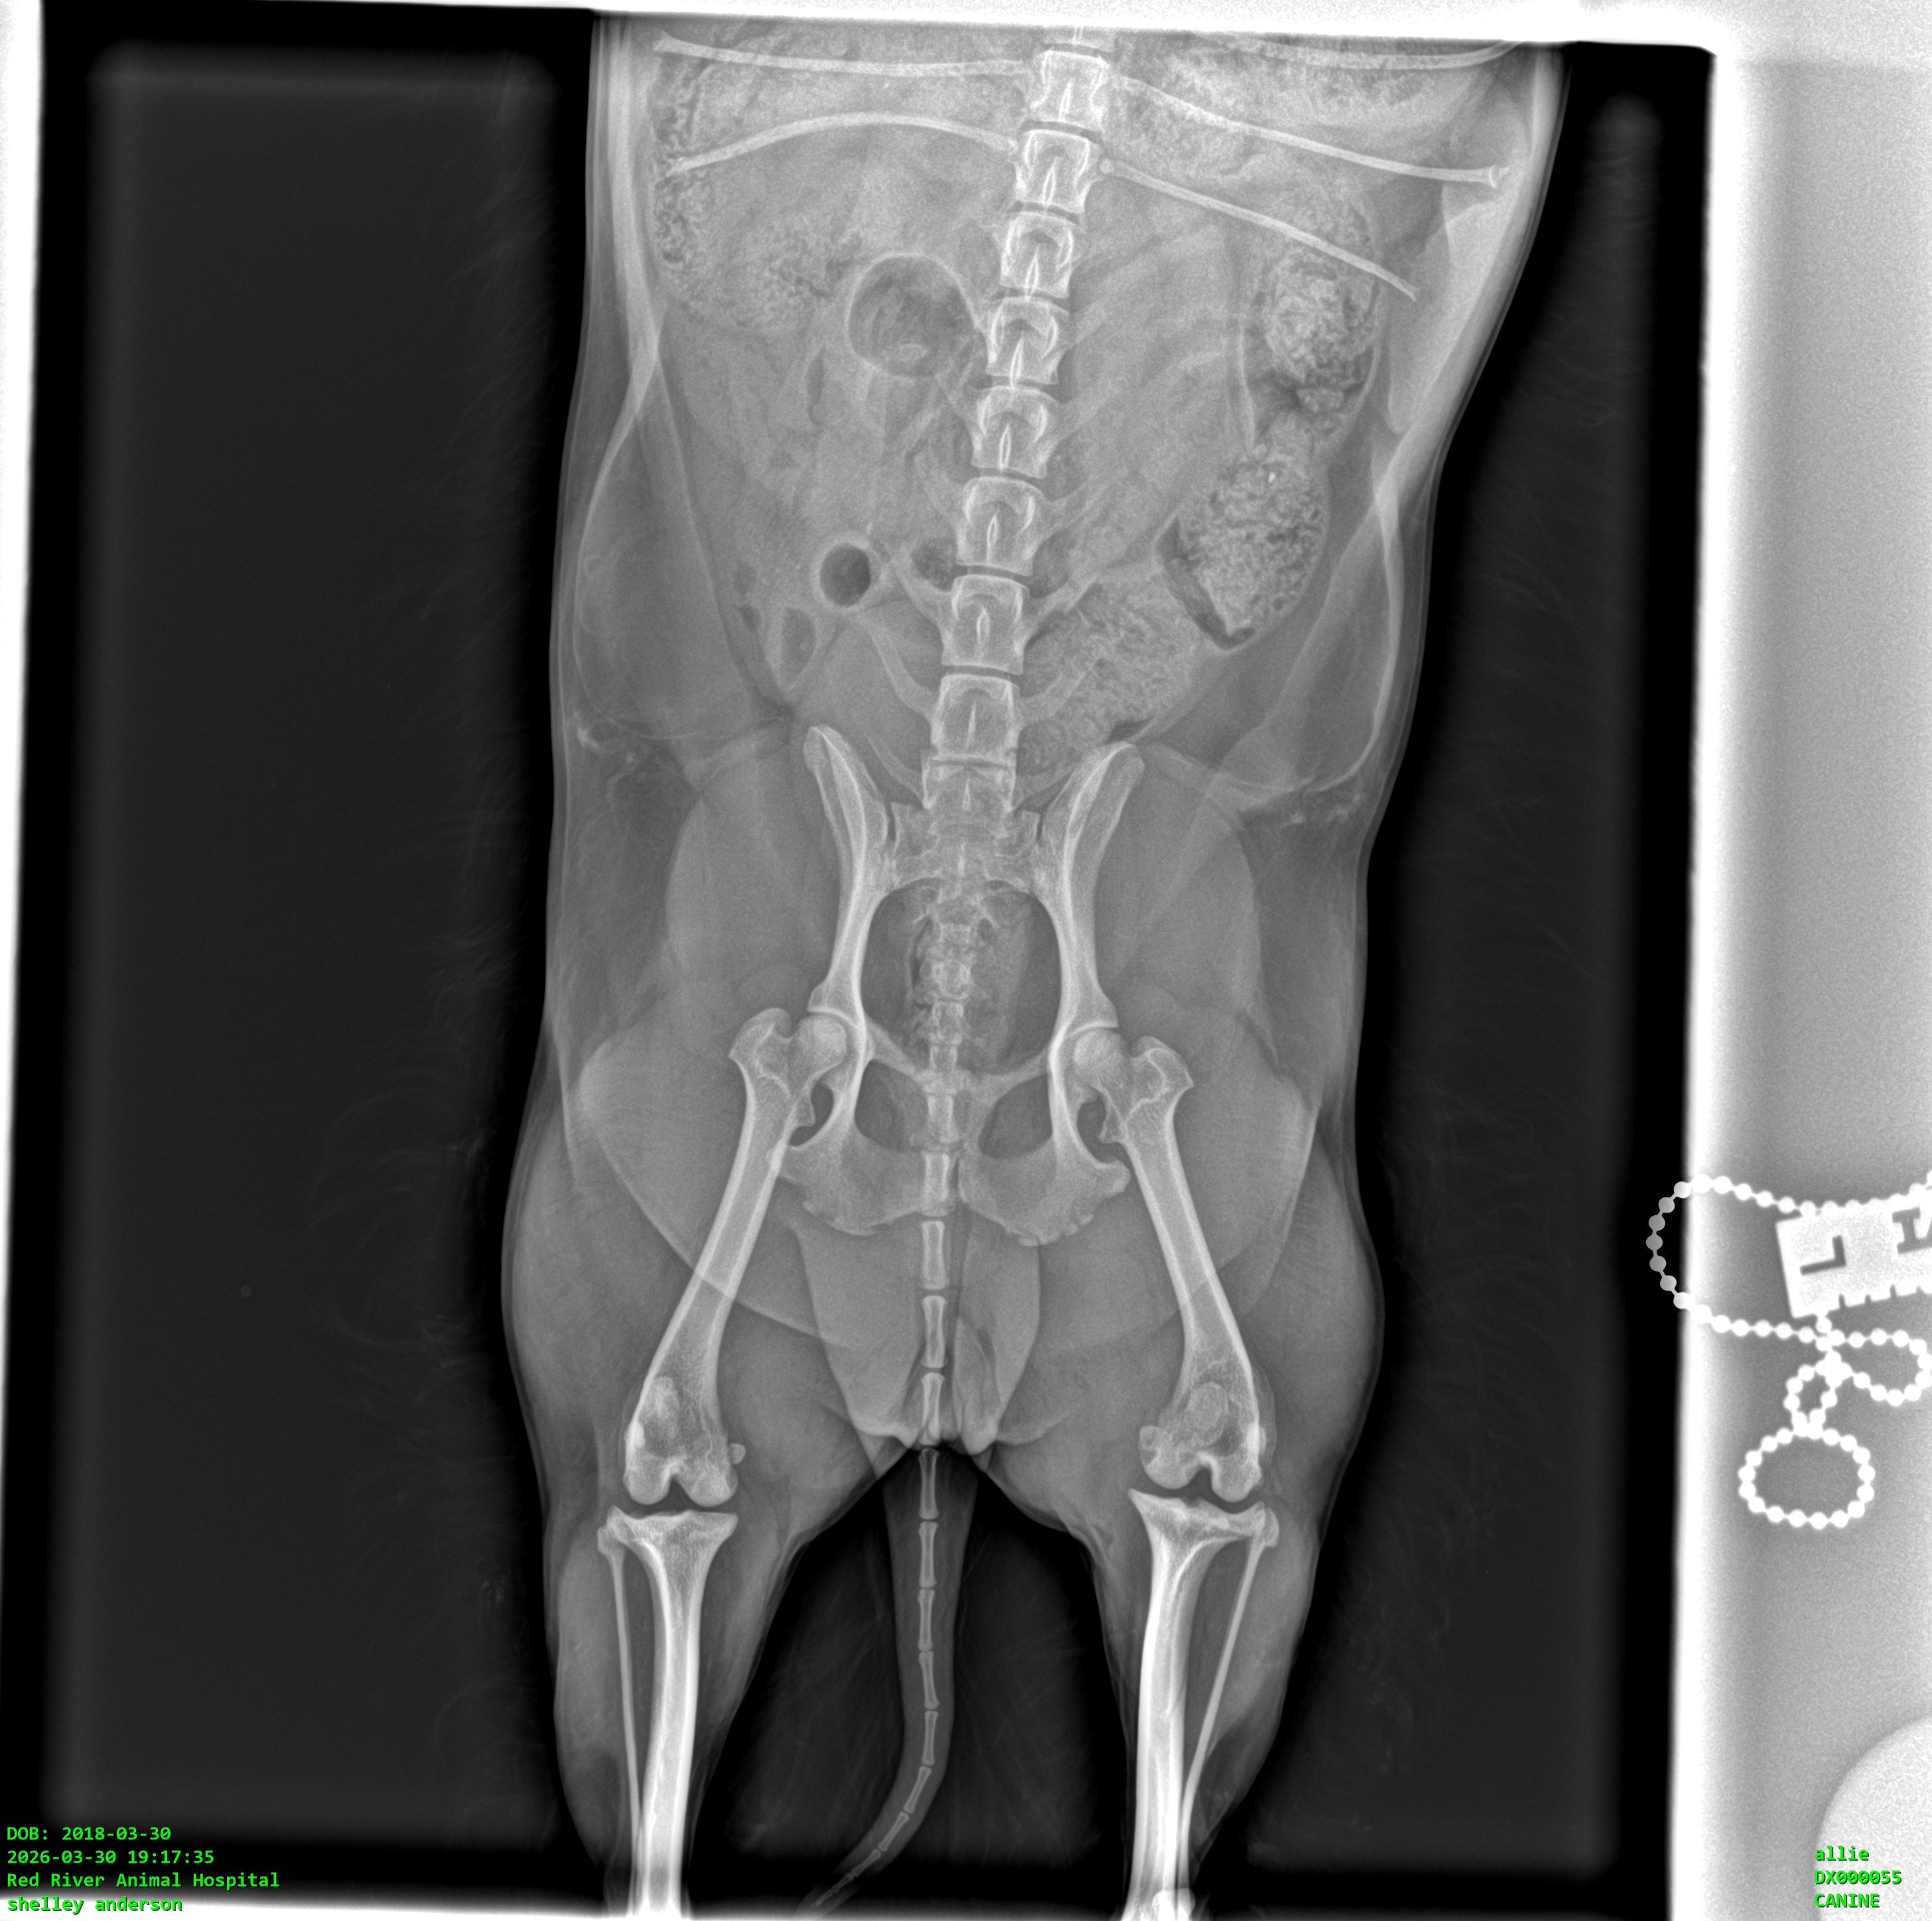

Allie is our 8-year-old Morkie, and she means absolutely everything to us, and especially to my mom. Allie is her whole world and goes everywhere with her. Recently, Allie was suddenly unable to put weight on her back leg. After taking her to the vet, we were told she has a torn ligament in her knee (CCL), which is very painful and requires surgery to properly fix.

Right now, she’s on pain medication and resting, but without surgery, there’s a risk of ongoing pain and long-term damage. We want to give her the best chance at a happy, comfortable life.

We were quoted between $5,000 and $5,500 for the surgery. If we don’t reach the full goal, the money will still go toward Allie’s care, like her medications, follow-up vet visits, rehabilitation, and possibly a more affordable surgical option or partial payment toward surgery. Nothing will go to waste, it will all be used for her treatment.